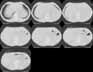

¥ Lung Cancer: Adenocarcinoma

8mmx4, Pitch 6, 384mm, 4-seconds, 150-mAs:

"High-speed screening mode."